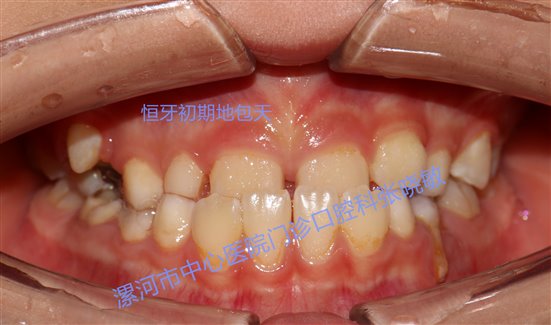

首先,什么是地包天?还有家长不知道的吗?赶紧来看一下,地包天就是前牙反颌,是下前牙覆盖上前牙,跟正常的上前牙覆盖下前牙正好相反。乳牙期地包天就是当孩子刚长出来第一幅乳牙时,就出现了前牙反颌的情况,这就是我们所说的乳牙地包天。

乳牙地包天如果不做及时的治疗,大部分换完牙后依然是地包天,且从乳牙期2岁半——恒前牙8岁左右替换完,这段时间下前牙错误的包括上前牙,就会导致上前牙发育受限,下前牙发育不受限,继而影响骨骼发育。